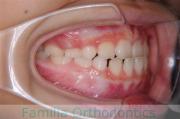

No.22V-029

- 主な症状:

- 叢生

- その他の症状:

- 上顎前突

- 年齢:

- 19歳

- 性別:

- 男性

- 抜歯部位

- 上:

- 8448

- 下:

- 主な使用装置:

- FEA 022

- 治療にかかった費用:

- 92万円

でこぼこを治したいということで来院されました。上下左右から親知らずも第一小臼歯も抜歯が必要で、歯科矯正アンカースクリューを併用して大臼歯を後ろに引っ張りながらの治療でした。3年弱、35回程度の通院が必要でした。

叢生が著しく、後戻りのリスクがあります。またアンカースクリューが必須のため、もしもスクリューが安定しないと、治療が難しく長くなってしまう恐れがありましたが、幸い脱落は見られませんでした。